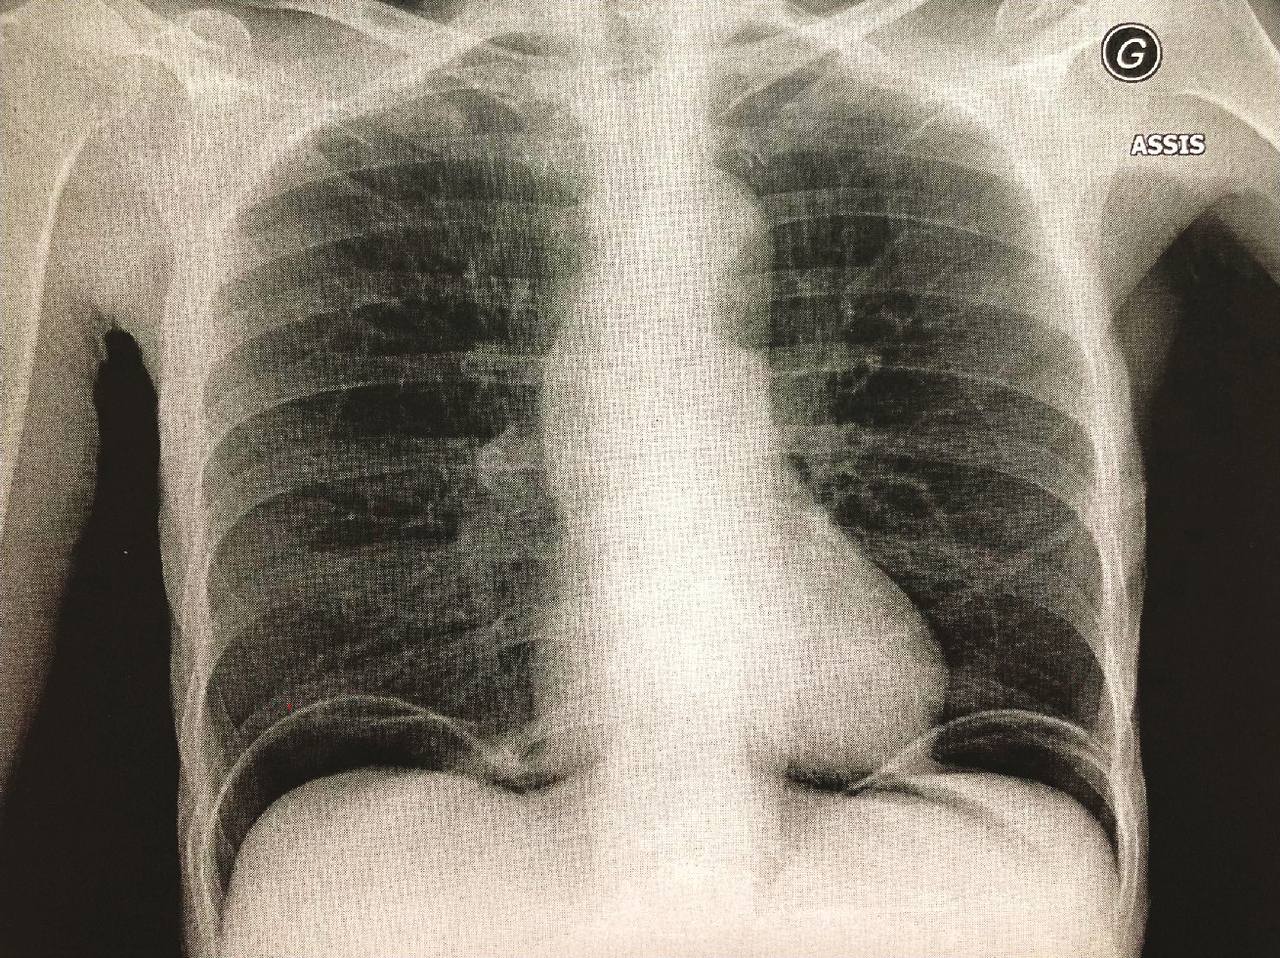

Quel est votre diagnostic ?

La bonne réponse est : Pneumopéritoine. Le cliché d'abdomen sans préparation, centré sur les coupoles et idéalement réalisé debout, permet de faire le diagnostic de pneumopéritoine, signant la perforation d'un organe creux (en l'absence de contexte postopératoire précoce). Il apparaît sous la forme d'une hyperclarté sous-diaphragmatique, bilatérale sur ce cliché.